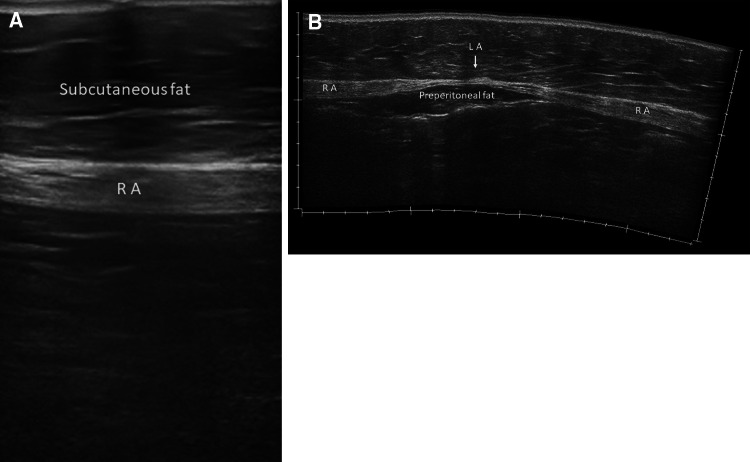

Fig. 9.

Muscular atrophy in an obese patient (a, b). On an ultrasound image, the infiltration of fat and fibrous tissue increases muscle echo intensity (a) and increases interface, and the muscles become whiter (b ultrasound panoramic image). There is marked hypertrophy of the subcutaneous adipose tissue. RA rectus abdominis, LA linea alba